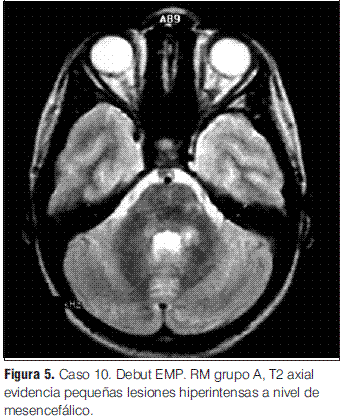

En nuestra serie no se presentaron recaídas ni recurrencias, con una media de tiempo de seguimiento de 3 años y 1 mes. Sin embargo, de los 12 pacientes con diagnóstico inicial de EMDA incluidos en este estudio, uno evolucionó a una esclerosis múltiple pediátrica (EMP), de acuerdo con los criterios propuestos por el consenso de expertos del “International Pediatric MS Study Group”, representando el 0,09 de la población en la que se pudo realizar seguimiento; la proporción de pacientes que tienen esta evolución varía en las diferentes series entre el 9% y el 40% (2,3); la presentación inicial de esta paciente con clínica polisintomática y con compromiso de conciencia (sintomatología EMDA-like) es una forma frecuente de debut de la EMP, lo cual subraya la importancia del seguimiento clínico e imagenológico sistematizado y prolongado para poder llegar a un diagnóstico definitivo [comunicación personal Tenembaun y colaboradores (33)]. Destacamos la afectación de los PEV sin repercusión clínica en este paciente, como signo de lesiones desmielinizantes silentes (4,2,17,27,28,34,35).

En cuanto a las RM de control, siete se normalizaron entre el año y los 3 años 7 meses; las cuatro en las que persistieron lesiones correspondieron tres de ellas a los pacientes con secuelas (tanto motoras como epilepsia secundaria y nivel cognitivo descendido) y una a un paciente que evolucionó a la esclerosis múltiple pediátrica (EMP) (tabla 3).

La mayoría de los EEG mostraron enlentecimiento de la actividad de fondo y descargas epileptiformes, hallazgos inespecíficos en relación a esta patología, como está descrito en otras series (2,4). Los PEV mostraron alteraciones en el paciente que evolucionó a la EMP, lo cual apoyaría la utilidad de los estudios electrofisiológicos en la detección de lesiones desmielinizantes asintomáticas frecuentes en niños con EMP (2,26,27). Los PEAT fueron normales en los dos pacientes evaluados con esta técnica.

Grupo A: EMDA a pequeñas placas, lesiones menores a 5 mm de diámetro.